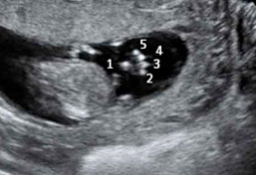

Ecografía de la semana 12

Los motivos por los que los ginecólogos recomiendan realizar una ecografía en la semana 12 de embarazo tienen que ver con el desarrollo anatómico y el tamaño del feto: ahora es lo bastante grande para comprobar si presenta anomalías. Además, ya se puede ver con claridad si hay uno o dos (o tres) bebés, calcular  la fecha probable de parto teniendo en cuenta la edad gestacional, y confirmar que esta coincide con el desarrollo del bebé. Se puede medir el llamado pliegue nucal (si sobrepasa unos parámetros a veces es indicio de problemas cromosómicos) y, si el bebé se deja, conocer su sexo.